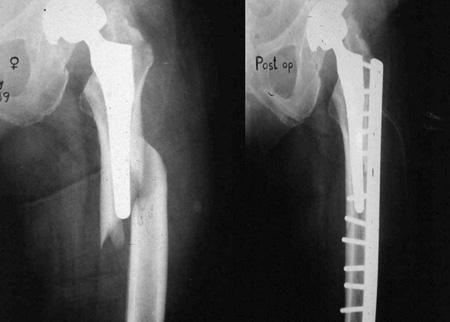

일상생활을 하다가 부러진 경우에도 똑같은 Vancouver Classification 을 사용합니다. 수술중과 큰 차이는 위치에 따라 골절을 나뉘고 B만 구체적으로 나누고 나머지는 그냥 A,C로 골절을 나뉩니다. STEM 이 헐거운 경우 B2, STEM 바로 아래는 B1, 삽입물 주변의 골절 또는 뼈가 부족한경우 B3로 이해하면 됩니다.